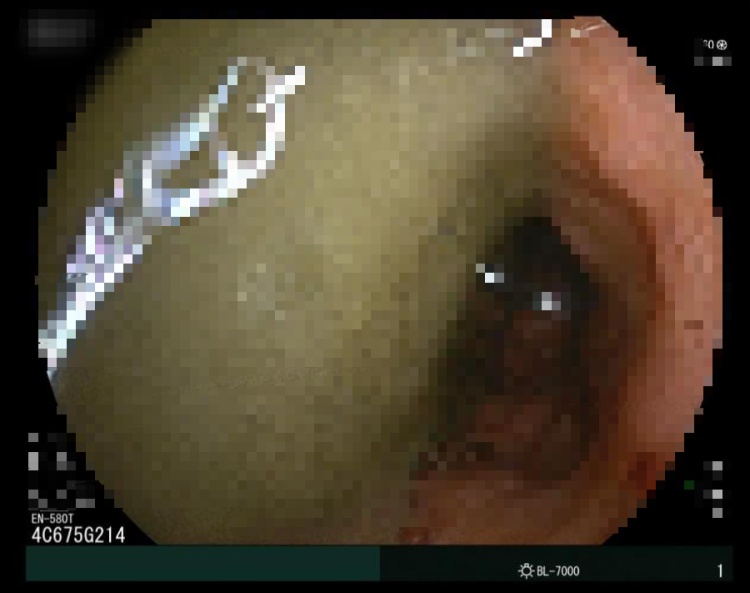

在麻醉团队的配合下,进展顺利。小肠镜入肛后,在距回盲瓣约70厘米处,医生发现“罪魁祸首”——一枚直径约10厘米、将肠腔完全堵塞的巨大粪石。郭勤主任果断施行“碎石术”,使用圈套器将粪石逐步分解粉碎,再用网篮带出碎石,如此往复。团队常规的小肠内镜下治疗1个多小时就可以完成,这次,历时4个多小时,堵塞管道一点点被清理通透,吸出2000多毫升粪水,肠梗阻最终解除。